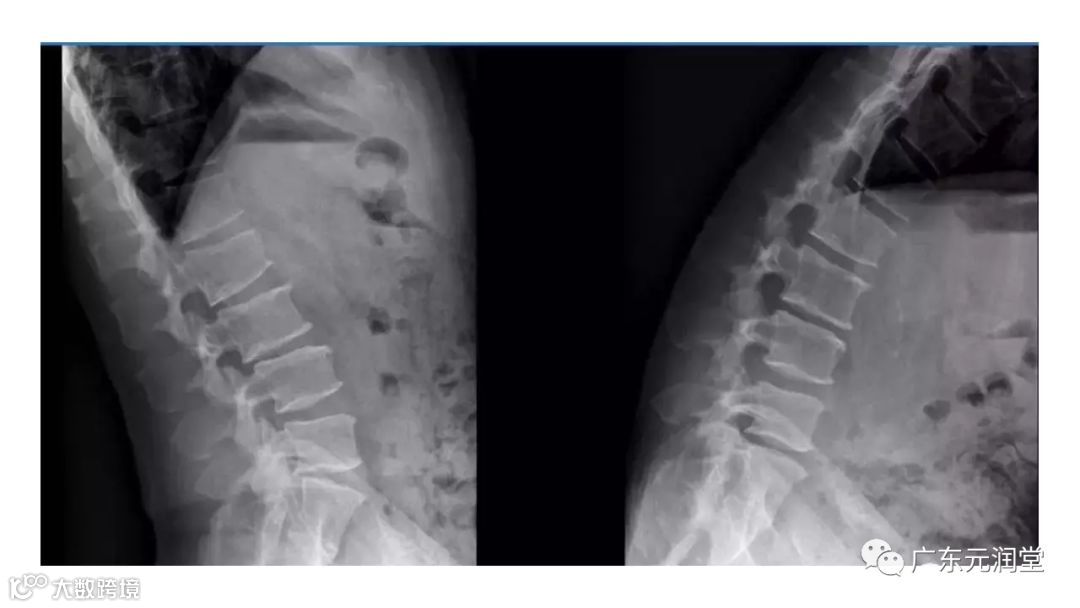

导读:X线检查操作规范之脊柱篇

X线检查操作规范之脊柱篇(值得收藏)